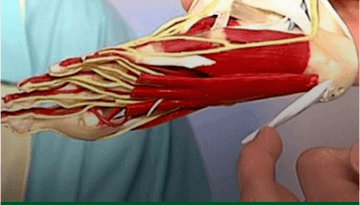

Боль и хруст в суставах, отеки и покраснения — это симптомы серьёзных проблем. Без своевременного лечения эти болезни становятся причиной полной потери подвижности и необратимой деформации суставов

«Заболевания опорно-двигательного аппарата – это всеобъемлющая проблема, с которой сталкивался практически каждый житель нашей Страны. Только остеоартрозом на сегодняшний день болеют 12% жителей Таджикистана независимо от возраста. Опасность таких болезней заключается в том, что они приводят к полной инвалидности. К счастью, несколько лет назад ведущими мировыми специалистами был разработан натуральный крем под названием Arteron. Как показала наша практика, применение крема Arteron позволяет избавиться от отечности, воспаления и боли в суставах и полностью восстановить их функции в домашних условиях всего за 2 недели...»